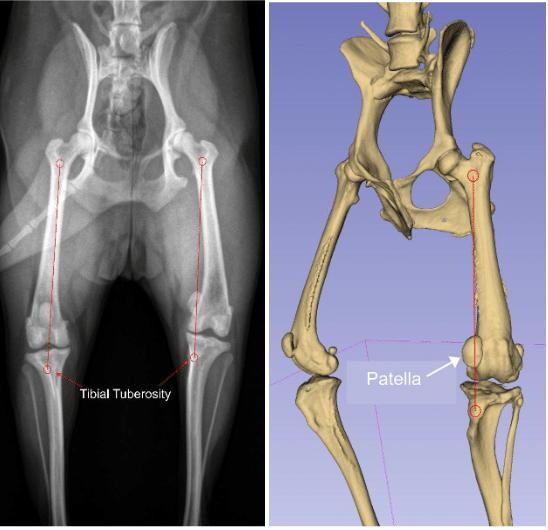

The images to the right (radiograph to the left and a virtual computed tomography (CT) reconstruction from a CT scan on the right) are from the same dog. The radiograph and CT both show how the dog patella is aligned with the quadriceps mechanism. The quadriceps is attached at two points (the small red circles), one at the top of the femur/thigh bone, and one at the tibial tuberosity (front of the shin bone). The quadriceps wants to run a (relatively) straight line between these two points. If the tibial tuberosity is too far to the inside of the tibia, as is the case for the abnormal dog knee above, the line of the quadriceps will be to the inside of the knee. The canine patella falls on that line of the quadriceps, and thus is not centered over the knee (either on the radiograph or the CT).